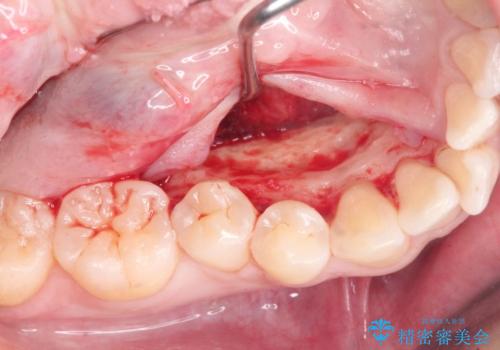

マウスピース矯正前に行う骨隆起の除去

- マウスピース矯正を行うにあたり、舌のスペースが狭くなってしまうことから骨隆起の除去を希望されました。

骨隆起の除去は30分ほどの小手術で終了します。